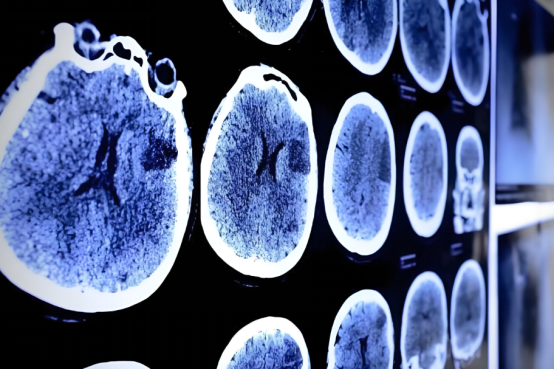

圖1 注射部位周圍的脊髓灰質與白質結構正常